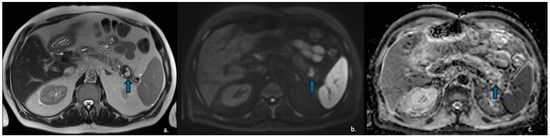

Pancreatic Cystic Lesions: From Basic Knowledge to Recent Guidelines

by Ginevra Danti, Ludovica Scalzone, Lavinia Mattolini, Matilde Anichini, Francesca Treballi, Linda Calistri, Diletta Cozzi and Vittorio Miele

Pancreatic cystic lesions (PCLs) are increasingly detected due to widespread use of cross-sectional imaging. They encompass a heterogeneous group of lesions, ranging from benign pseudocysts and serous cystic neoplasms (SCNs) to premalignant mucinous cystic neoplasms (MCNs) and intraductal papillary mucinous neoplasms (IPMNs), as [...] Read more.

Pancreatic cystic lesions (PCLs) are increasingly detected due to widespread use of cross-sectional imaging. They encompass a heterogeneous group of lesions, ranging from benign pseudocysts and serous cystic neoplasms (SCNs) to premalignant mucinous cystic neoplasms (MCNs) and intraductal papillary mucinous neoplasms (IPMNs), as well as rare malignant entities such as solid pseudopapillary epithelial neoplasm (SPENs) and cystic pancreatic neuroendocrine tumors (cystic PanNETs). Management of PCLs depends on their malignant potential; therefore, an accurate classification is essential for optimizing treatment. This narrative review summarizes current knowledge on the epidemiology, imaging characteristics, diagnosis, and management of PCLs, highlighting the role of CT, MRI, MRCP, and endoscopic ultrasound. Recent advances in radiomics for lesion characterization and risk stratification, particularly in IPMNs, are discussed. Full article

Show Figures

Figure 1